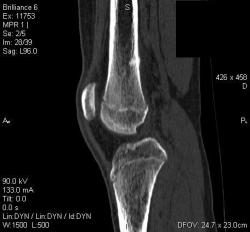

Мальчик 15 лет. Несколько месяцев назад начали беспокоить боли в коленных суставах. Травмы не было. Ребёнку был выставлен диагноз: болезнь Шлаттера, назначено лечение. На фоне лечения отмечалось значительное усиление болей, боли локализовались в левом коленном суставе. При дообследовании выявлена следующая рентгенологическая картина. Наши рентгенологи настаивают на срастающемся переломе. Но: 1) перелом без травмы? 2) бедро так не ломается

Локальный гиперостоз, выраженный болевой синдром, структура губчатого вещества диафиза не изменена наводит только на остеойд-остеому.

Согласна с Ola-la - рентгенологическая картина более всего соответствует стрессорному перелому, хотя для него характерна локализация в б/берцовой кости. Меня однако, смущает и настораживает клиника - это как раз тот случай, когда я бы не дала 100% гарантии, что так не может манифестировать остеосаркома... Поскольку другие методы (МРТ, сцинтиграфия) вряд ли помогут, я бы взяла пациента на короткое ( 2недели - месяц) динамическое наблюдение.

Да, на мой взгляд, состояние после обычного "травматического перелома" (трещина), не думаю, что имел место "патологический перелом", так как костная ткань "патологически изменена" минимально. "Перистальная реакция"локальная тоже есть, на КТ "локальная  зона склероза" - все это свидетельствует именно об этом. Хотя в памяти у меня хорошо отложился Ваш последний случай о локальном утолщении кортикального слоя, когда "яйца в гнезде" еще не было. То, что анамнестически "травмы не было" - ничего не значит. Вы, по всей видимости, тоже часто встречались с такими случаями, когда ребенок не акцентировал внимание на "травме", как таковой, хотя клиника есть, боль есть. Конечно, рентгенограммы - не дай бог - ни скиалогии, ни структуры.